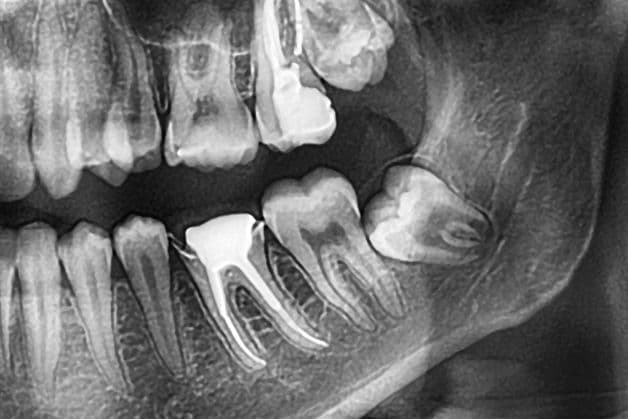

Hình ảnh răng khôn mọc lệch, ngầm, đâm vào răng bên cạnh.

– Răng khôn mọc lệch, ngầm, đâm vào răng bên cạnh